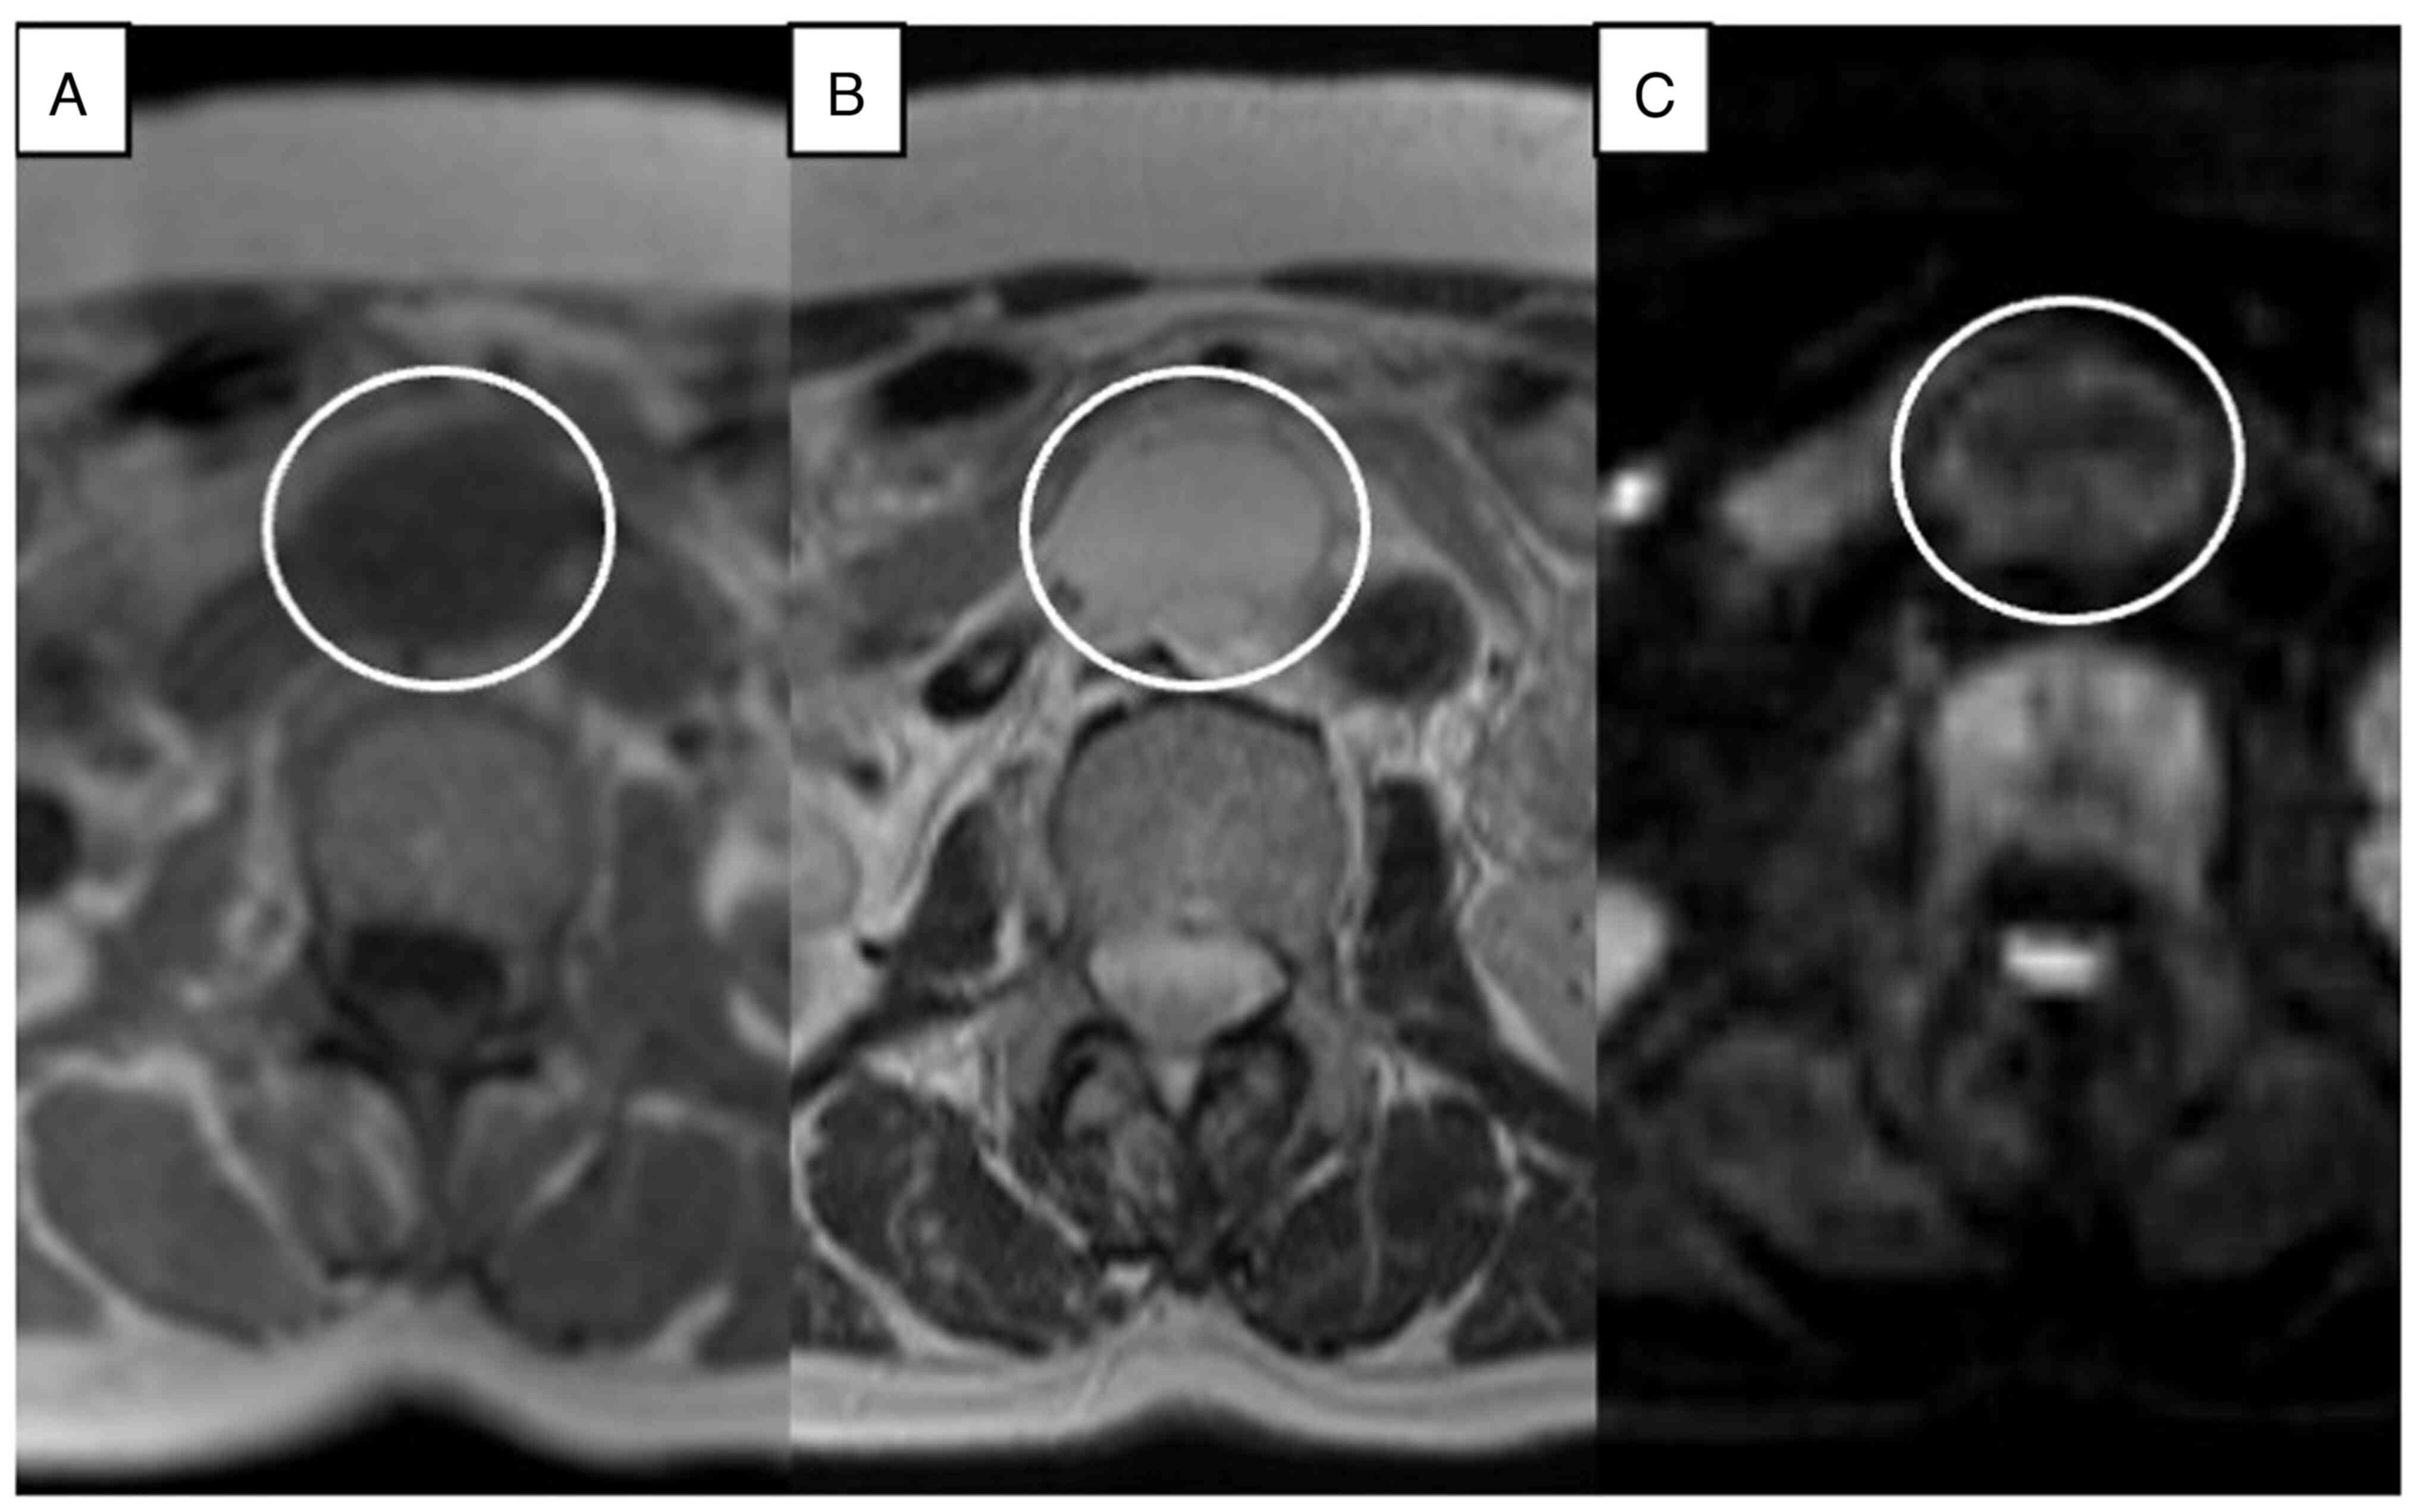

Anastomosing hemangioma (AH) is rare and a newly recognized variant of capillary hemangioma that is mostly found in the genitourinary tract. Additionally, AH is sometimes difficult to diagnose without pathological specimens. It is difficult to diagnose preoperatively due to the lack of specific clinical and radiologic appearance. The present report describes the imaging features from a radiological perspective and outlines the clinicopathologic features and treatment options. A 67‑year‑old woman was referred to Dokkyo Medical University Saitama Medical Center (Koshigaya, Japan) for a retroperitoneal tumor that was identified at a medical checkup 4 years prior. The patient had no symptoms, no abnormal physical signs and no past medical or specific family history. Routine blood tests were all within the normal ranges. A nonenhanced CT scan showed a circular, homogenous, well‑circumscribed retroperitoneal tumor that was ~32x23 mm in size, between the abdominal aorta and the inferior vena cava, and just below the left renal vein. On a contrast‑enhanced multidetector CT scan, the tumor showed heterogeneous septal enhancement in the arterial phase and persistent enhancement in the portal phase. The tumor was diagnosed as a benign neurogenic tumor or a retroperitoneal cavernous hemangioma at the time, and the patient was intended to be followed up at the outpatient clinic. However, it gradually increased to a maximum diameter of 35 mm over 4 years. Finally, it was completely resected by open laparotomy and pathologically diagnosed as AH. Retroperitoneal hemangioma is extremely rare in adulthood and has been confirmed in only 1‑3% of all retroperitoneal tumors. To the best of our knowledge, only 6 cases of para‑aortic AH have been reported. The incidence of this variant is very low. However, AH may be included in the differential diagnosis when a slowly progressing heterogeneous mass appears in the para‑aortic region that exhibits a CT‑enhanced pattern similar to a typical cavernous hemangioma.